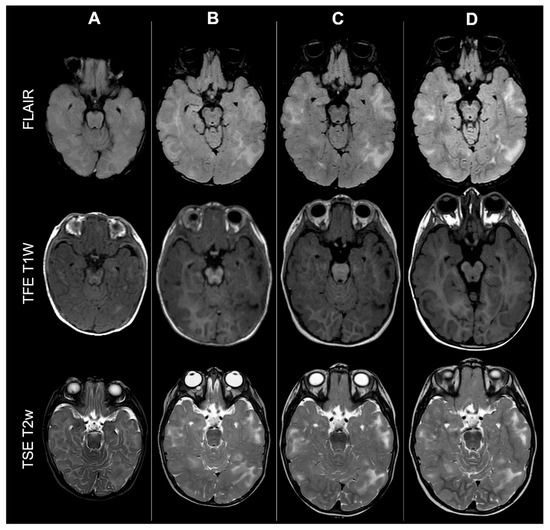

Concerning total lesion count, the interobserver agreement was excellent, with an ICC of 0.91 (95% CI: 0.87–0.95). At baseline, the total number of CTs identified across the cohort was 918 (mean ± SD = 16.1 ± 12.4), whereas at the last available MRI follow-up, the overall count increased to 1070 (mean ± SD = 18.8 ± 13.3), corresponding to a net gain of 152 CTs, equal to a relative variation of +17%. When stratified by tuber type, distinct trajectories were observed over time. Type A CTs, which were relatively abundant at diagnosis (N = 303, mean ± SD = 5.3 ± 7.0), decreased to 255 (mean ± SD = 4.5 ± 5.9) at follow-up, yielding a reduction of 48 lesions (−16%). Conversely, type B CTs showed an opposite trend, increasing from 438 (mean ± SD = 7.7 ± 8.4) at baseline to 556 (mean ± SD = 9.8 ± 8.6) at follow-up, corresponding to a net increase of 118 tubers (+27%). An example of MRI signal evolution from tuber A to tuber B is shown in Figure 1. Similarly, type C1 CTs rose from 160 (mean ± SD = 2.8 ± 4.8) to 220 (mean ± SD = 3.9 ± 5.8), with a net gain of 60 tubers (+38%). Type C2 CTs, initially rare at diagnosis (N = 14, mean ± SD = 0.2 ± 0.8), markedly expanded to 33 (mean ± SD = 0.6 ± 1.5), accounting for an increase of 19 CTs (+136%). Finally, type D CTs were only sporadically encountered, with a modest increase from 3 (mean ± SD = 0.1 ± 0.3) to 6 (mean ± SD = 0.1 ± 0.4), equating to a 100% variation. The observed increment of type C2 tubers was attributable almost exclusively to the progressive transformation of pre-existing type B lesions and, more prominently, type C1 lesions, while the increase in type C1 tubers reflected the gradual conversion of both type A and type B CTs that were already detectable at disease onset. An example of MRI signal evolution from tuber B to C1 is shown in Figure 2, while from tuber C1 to C2 in Figure 3. Only in one patient was a type C1 tuber newly identified at follow-up without clear evidence at baseline. In contrast, newly apparent tubers emerging over time but not clearly visible on baseline scans were most frequently represented by type A and type B lesions. Type D tubers were rare overall and were identified in only six lesions from four patients with a particularly high lesion burden; in all but one case they represented the evolution of type A or type B CTs (an example of MRI signal evolution from tuber A to tuber D is shown in Figure 4), while in a single case they were associated with adjacent subtle calcific foci. Overall descriptive data are summarized in Table 1.

Figure 1.

Left occipital tuber transition from type A to B at three different timepoints in a male patient diagnosed with TSC1.

Figure 5.

Effect of myelination on cerebral cortical tubers’ count: MRI scans from the same male TSC2 patient acquired at four different timepoints (respectively: 6 months old—column A; 18 months old—column B; 36 months old—column C; 4 years old—column D, showing how incomplete myelination in early infancy may impact tubers detection by reducing contrast with surrounding brain tissue.